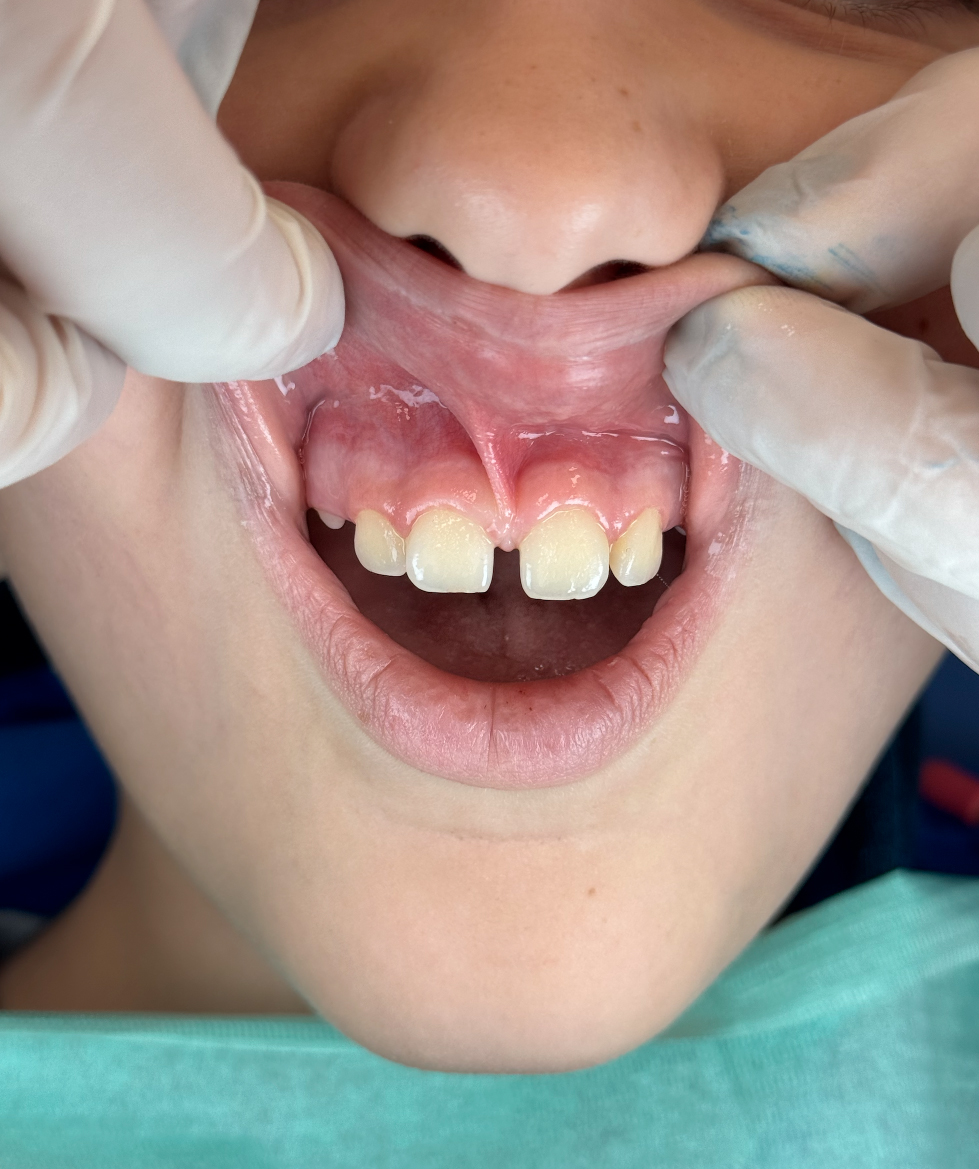

Ti è mai capitato di notare uno spazio eccessivo tra gli incisivi superiori di tuo figlio o di avvertire una tensione anomala alla gengiva? Spesso la causa risiede nel frenulo, una piccola struttura anatomica che può richiedere un intervento correttivo chiamato frenulectomia.

- Spazio tra i denti: Un frenulo labiale superiore troppo spesso o con un’inserzione molto bassa agisce come una barriera fisica tra i due incisivi centrali. Questo impedisce ai denti di avvicinarsi naturalmente, creando un vuoto che spesso non si chiude nemmeno con la crescita dei denti permanenti.

- Chiusura del Diastema: Nel caso dei bambini, un frenulo troppo basso può impedire ai due incisivi centrali di avvicinarsi, creando il classico spazio vuoto (diastema). La rimozione del frenulo permette ai denti di allinearsi correttamente.